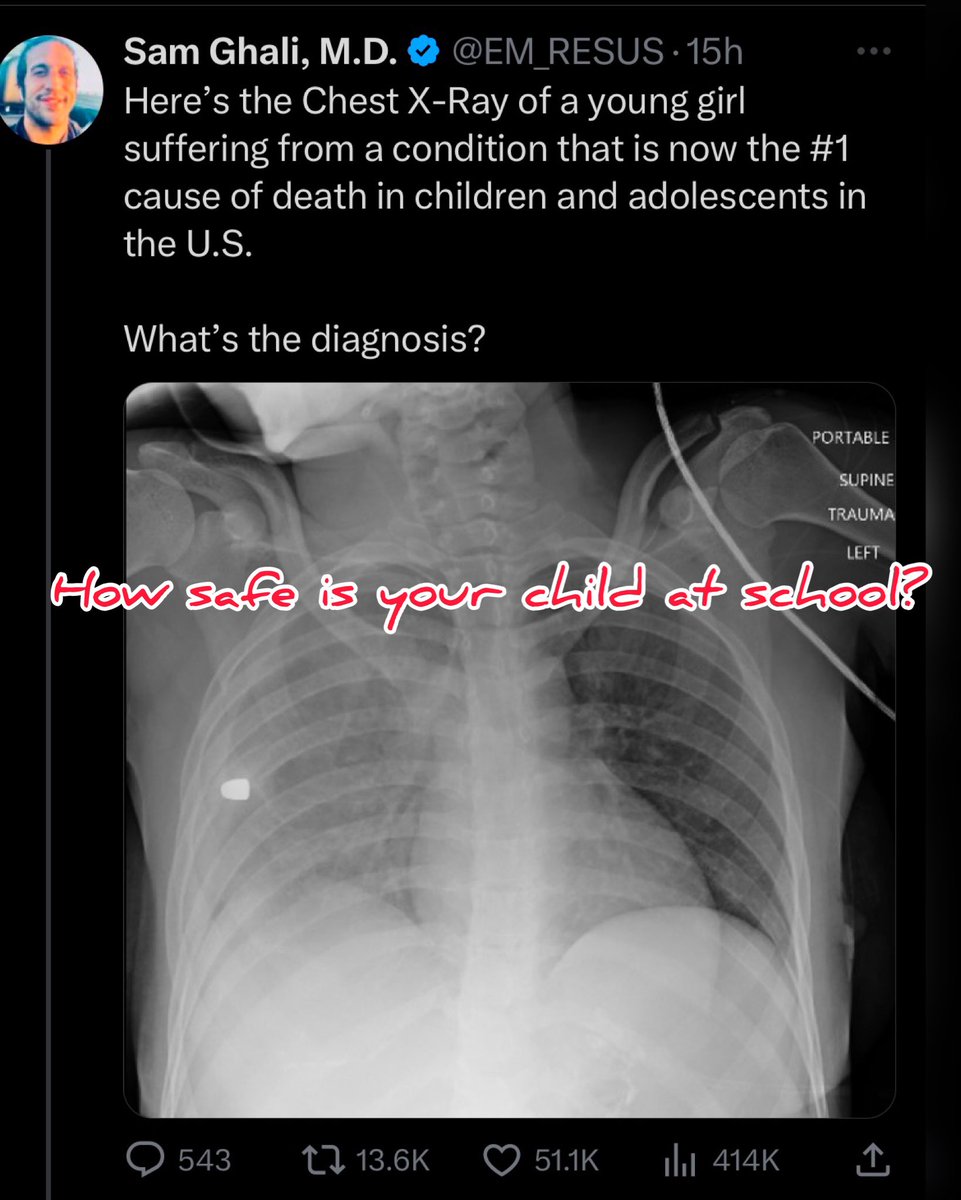

How do school safety efforts compromise/enhance the quality of the learning environment? Most states mandate drills, which can have long-lasting negative mental & physical consequences to the students & staff. #activeshooter #schoolsafety

Fox2Sierra LLC tweet media